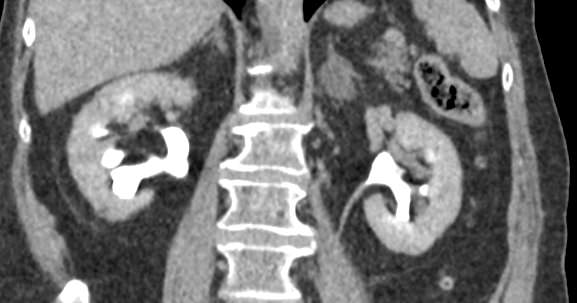

Мультиспиральная компьютерная томография почек и мочевыводящих путей  является высокоинформативным методом исследования, основанном на использовании воздействия рентгеновских лучей на органы и ткани человека. Методика предусматривает послойное сканирование области почек, мочевыводящих путей и получение снимков исследуемой области в мельчайших подробностях.

Для улучшения визуализации патологических очагов (различных кист или новообразований) в некоторых случаях дополнительно применяется контрастное усиление. Для этого пациенту внутривенно вводится йодсодержащее контрастное вещество, которое накапливается в патологически измененных участках и вызывает их яркое контрастирование на фоне здоровых тканей.

МСКТ почек и мочевыводящих путей с контрастированием позволяет выявить опухолевые образования на ранних стадиях, отличить доброкачественную опухоль от злокачественной, определить размеры опухоли, точную локализацию и степень распространения в окружающие ткани. Компьютерная томография почек с внутривенным болюсным контрастированием необходима для определения тактики лечения и объема оперативного вмешательства.